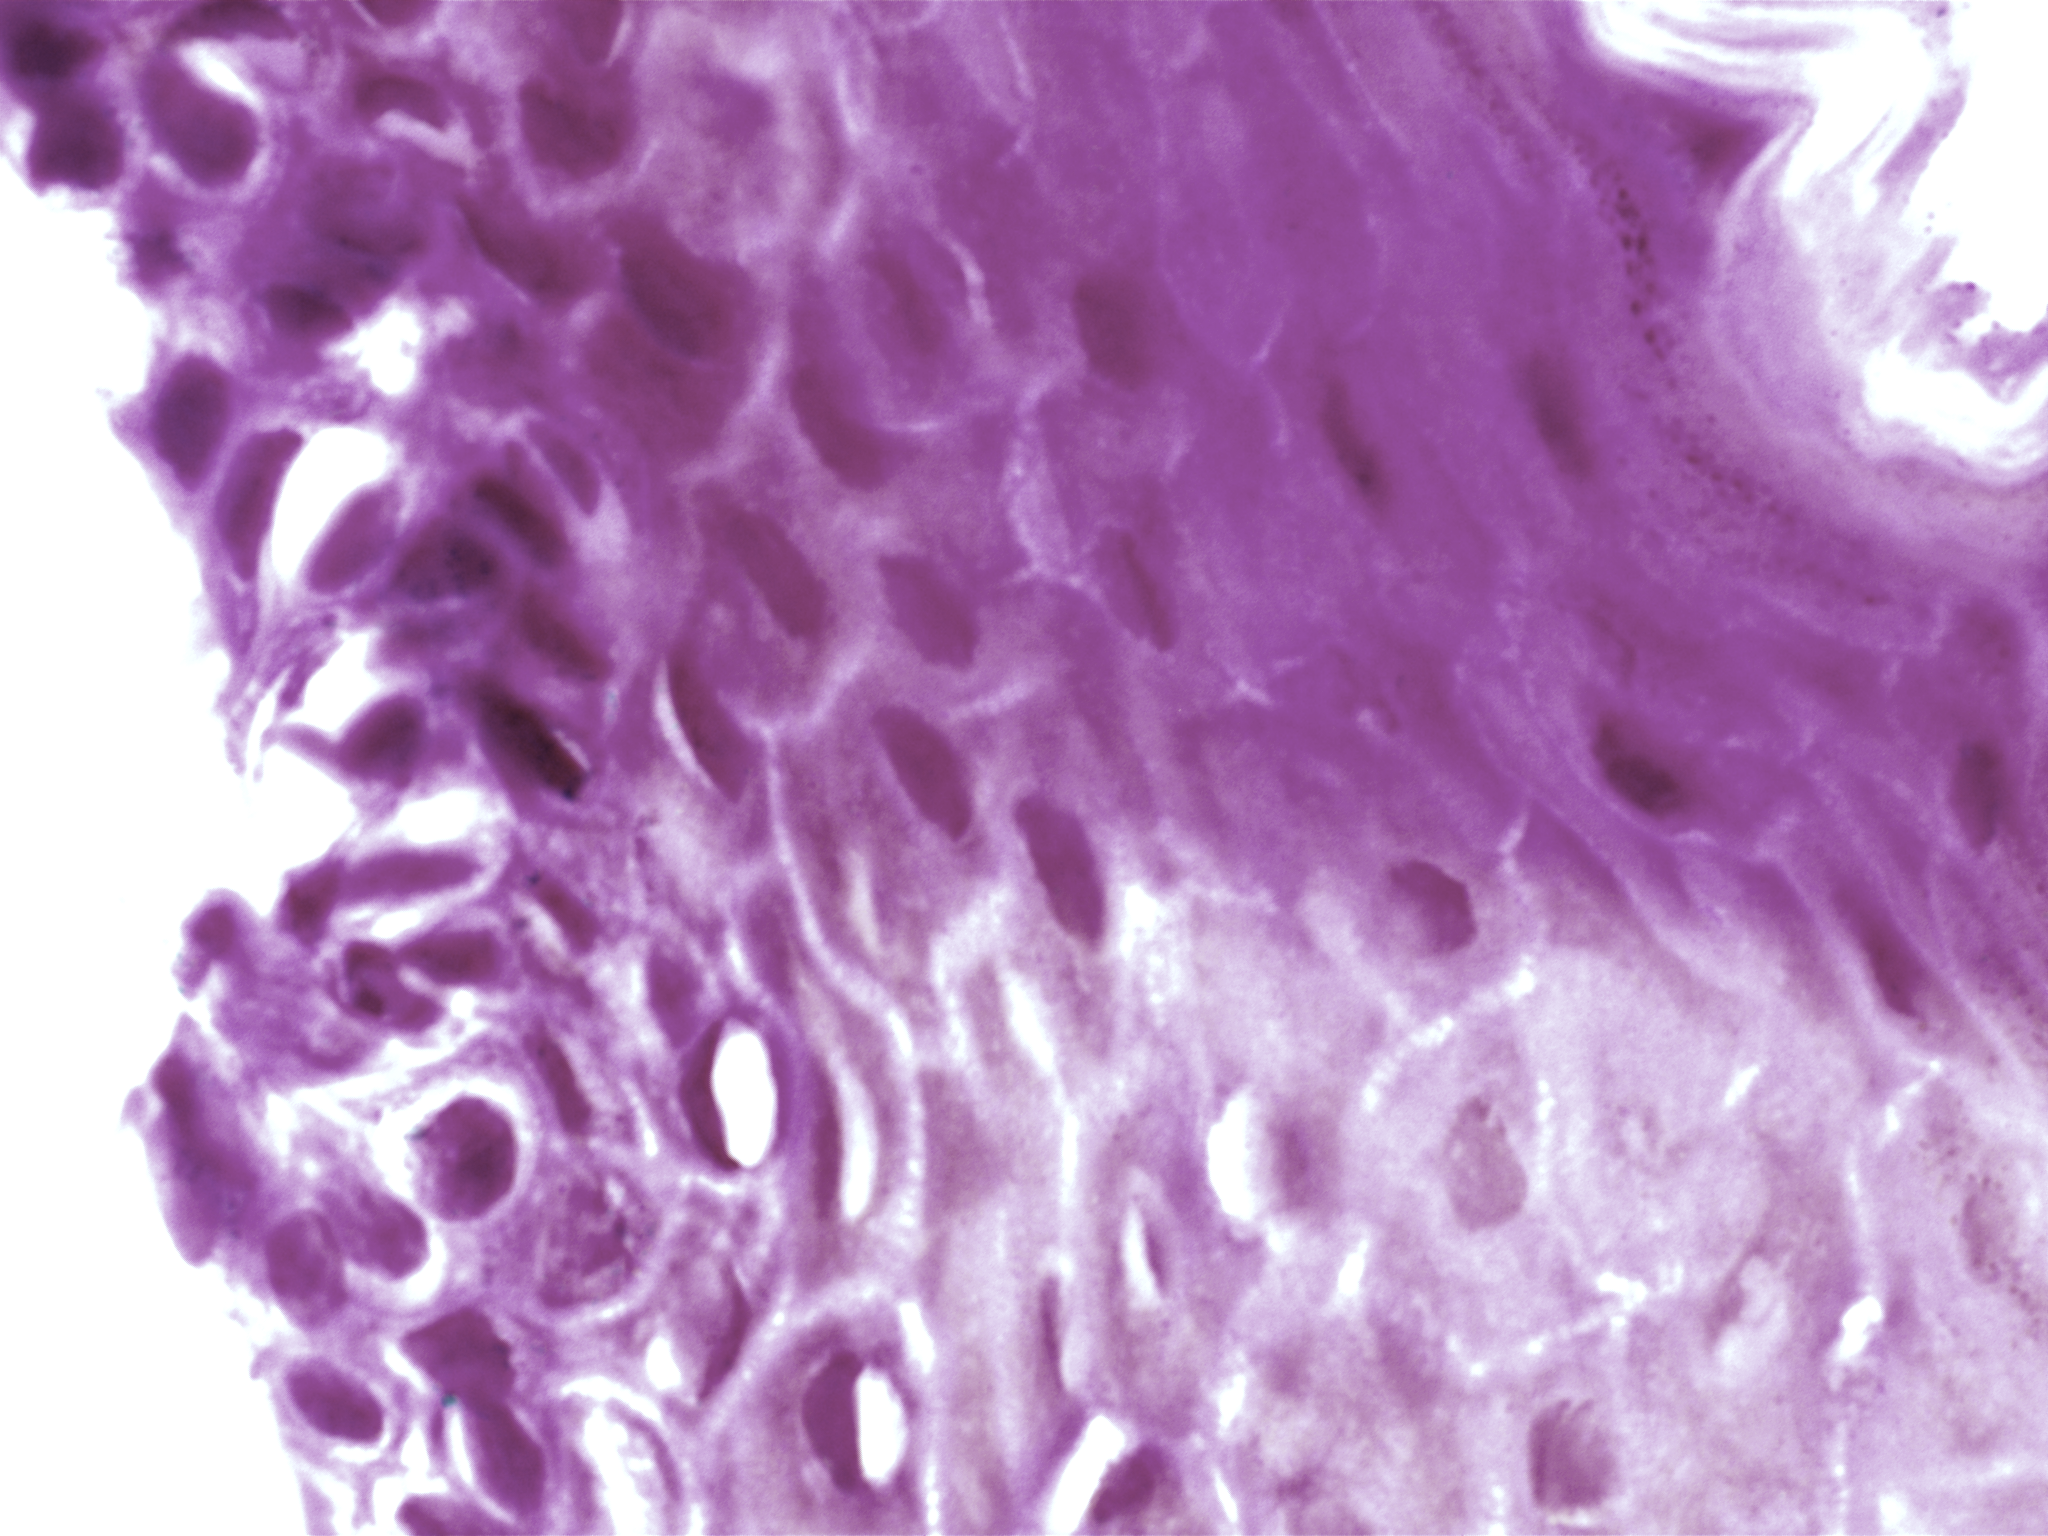

| Title: | High-resolution AI image dataset for diagnosing oral submucous fibrosis and squamous cell carcinoma |

| Description: | Oral cancer is a global health challenge with a difficult histopathological diagnosis. The accurate histopathological interpretation of oral cancer tissue samples remains difficult. However, early diagnosis is very challenging due to a lack of experienced pathologists and inter- observer variability in diagnosis. The application of artificial intelligence (deep learning algorithms) for oral cancer histology images is very promising for rapid diagnosis. However, it requires a quality annotated dataset to build AI models. We present ORCHID (ORal Cancer Histology Image Database), a specialized database generated to advance research in AI-based histology image analytics of oral cancer and precancer. The ORCHID database is an extensive multicenter collection of high-resolution images captured at 1000X effective magnification (100X objective lens), encapsulating various oral cancer and precancer categories, such as oral submucous fibrosis (OSMF) and oral squamous cell carcinoma (OSCC). Additionally, it also contains grade-level sub-classifications for OSCC, such as well- differentiated (WD), moderately-differentiated (MD), and poorly-differentiated (PD). The database seeks to aid in developing innovative artificial intelligence-based rapid diagnostics for OSMF and OSCC, along with subtypes. |

| Imaging Type: | Histopathology (HISTO) |

| The ORCHID database is an extensive multicenter collection of high-resolution images captured at 1000X effective magnification (100X objective lens). Tissue slides were collected with the approval of an ethical committee from the participating hospitals and research institutions. The buccal mucosa tissue samples were collected for three classes, normal, OSMF, and OSCC, with grade-wise annotation from the pathologists at each hospital. Biopsy samples of normal, OSMF and OSCC tissues underwent H&E staining. The staining procedure was conducted either in-house or outsourced to different laboratories. To eliminate staining variations across different laboratories, the preparation of H&E slides involved five histopathology labs, each utilizing their own independently developed and optimized protocols for the staining process. Following staining, the samples were examined under a microscope by a skilled histopathologist to assess cellular morphology, and tissue architecture, and identify any distinctive features or abnormalities specific to each sample type. This evaluation by the histopathologist involved grading the tissue slides for OSCC and OSMF, as well as differentiating between normal and diseased tissue sections. Images were acquired using a 1000X magnification (100X objective) lens from Leedz microimaging (LMI) bright field microscopy. To capture the images consistently, we utilized ToupView imaging software, which was configured for automatic adjustments. This setting applies to both white balance and camera settings, thereby standardizing the image acquisition process across different slides. The images of the H&E stained slides were captured at 1000X magnification(100X objective lens). By setting the ToupView software to automatically adjust white balance and camera settings, we aimed to minimize human intervention and the variability it introduces. This approach ensures that the images are not only consistent but also replicable in different laboratory settings, provided similar equipment and software settings are used. We collected approximately 100–150 images per tissue slide, which were stored in PNG file format. |